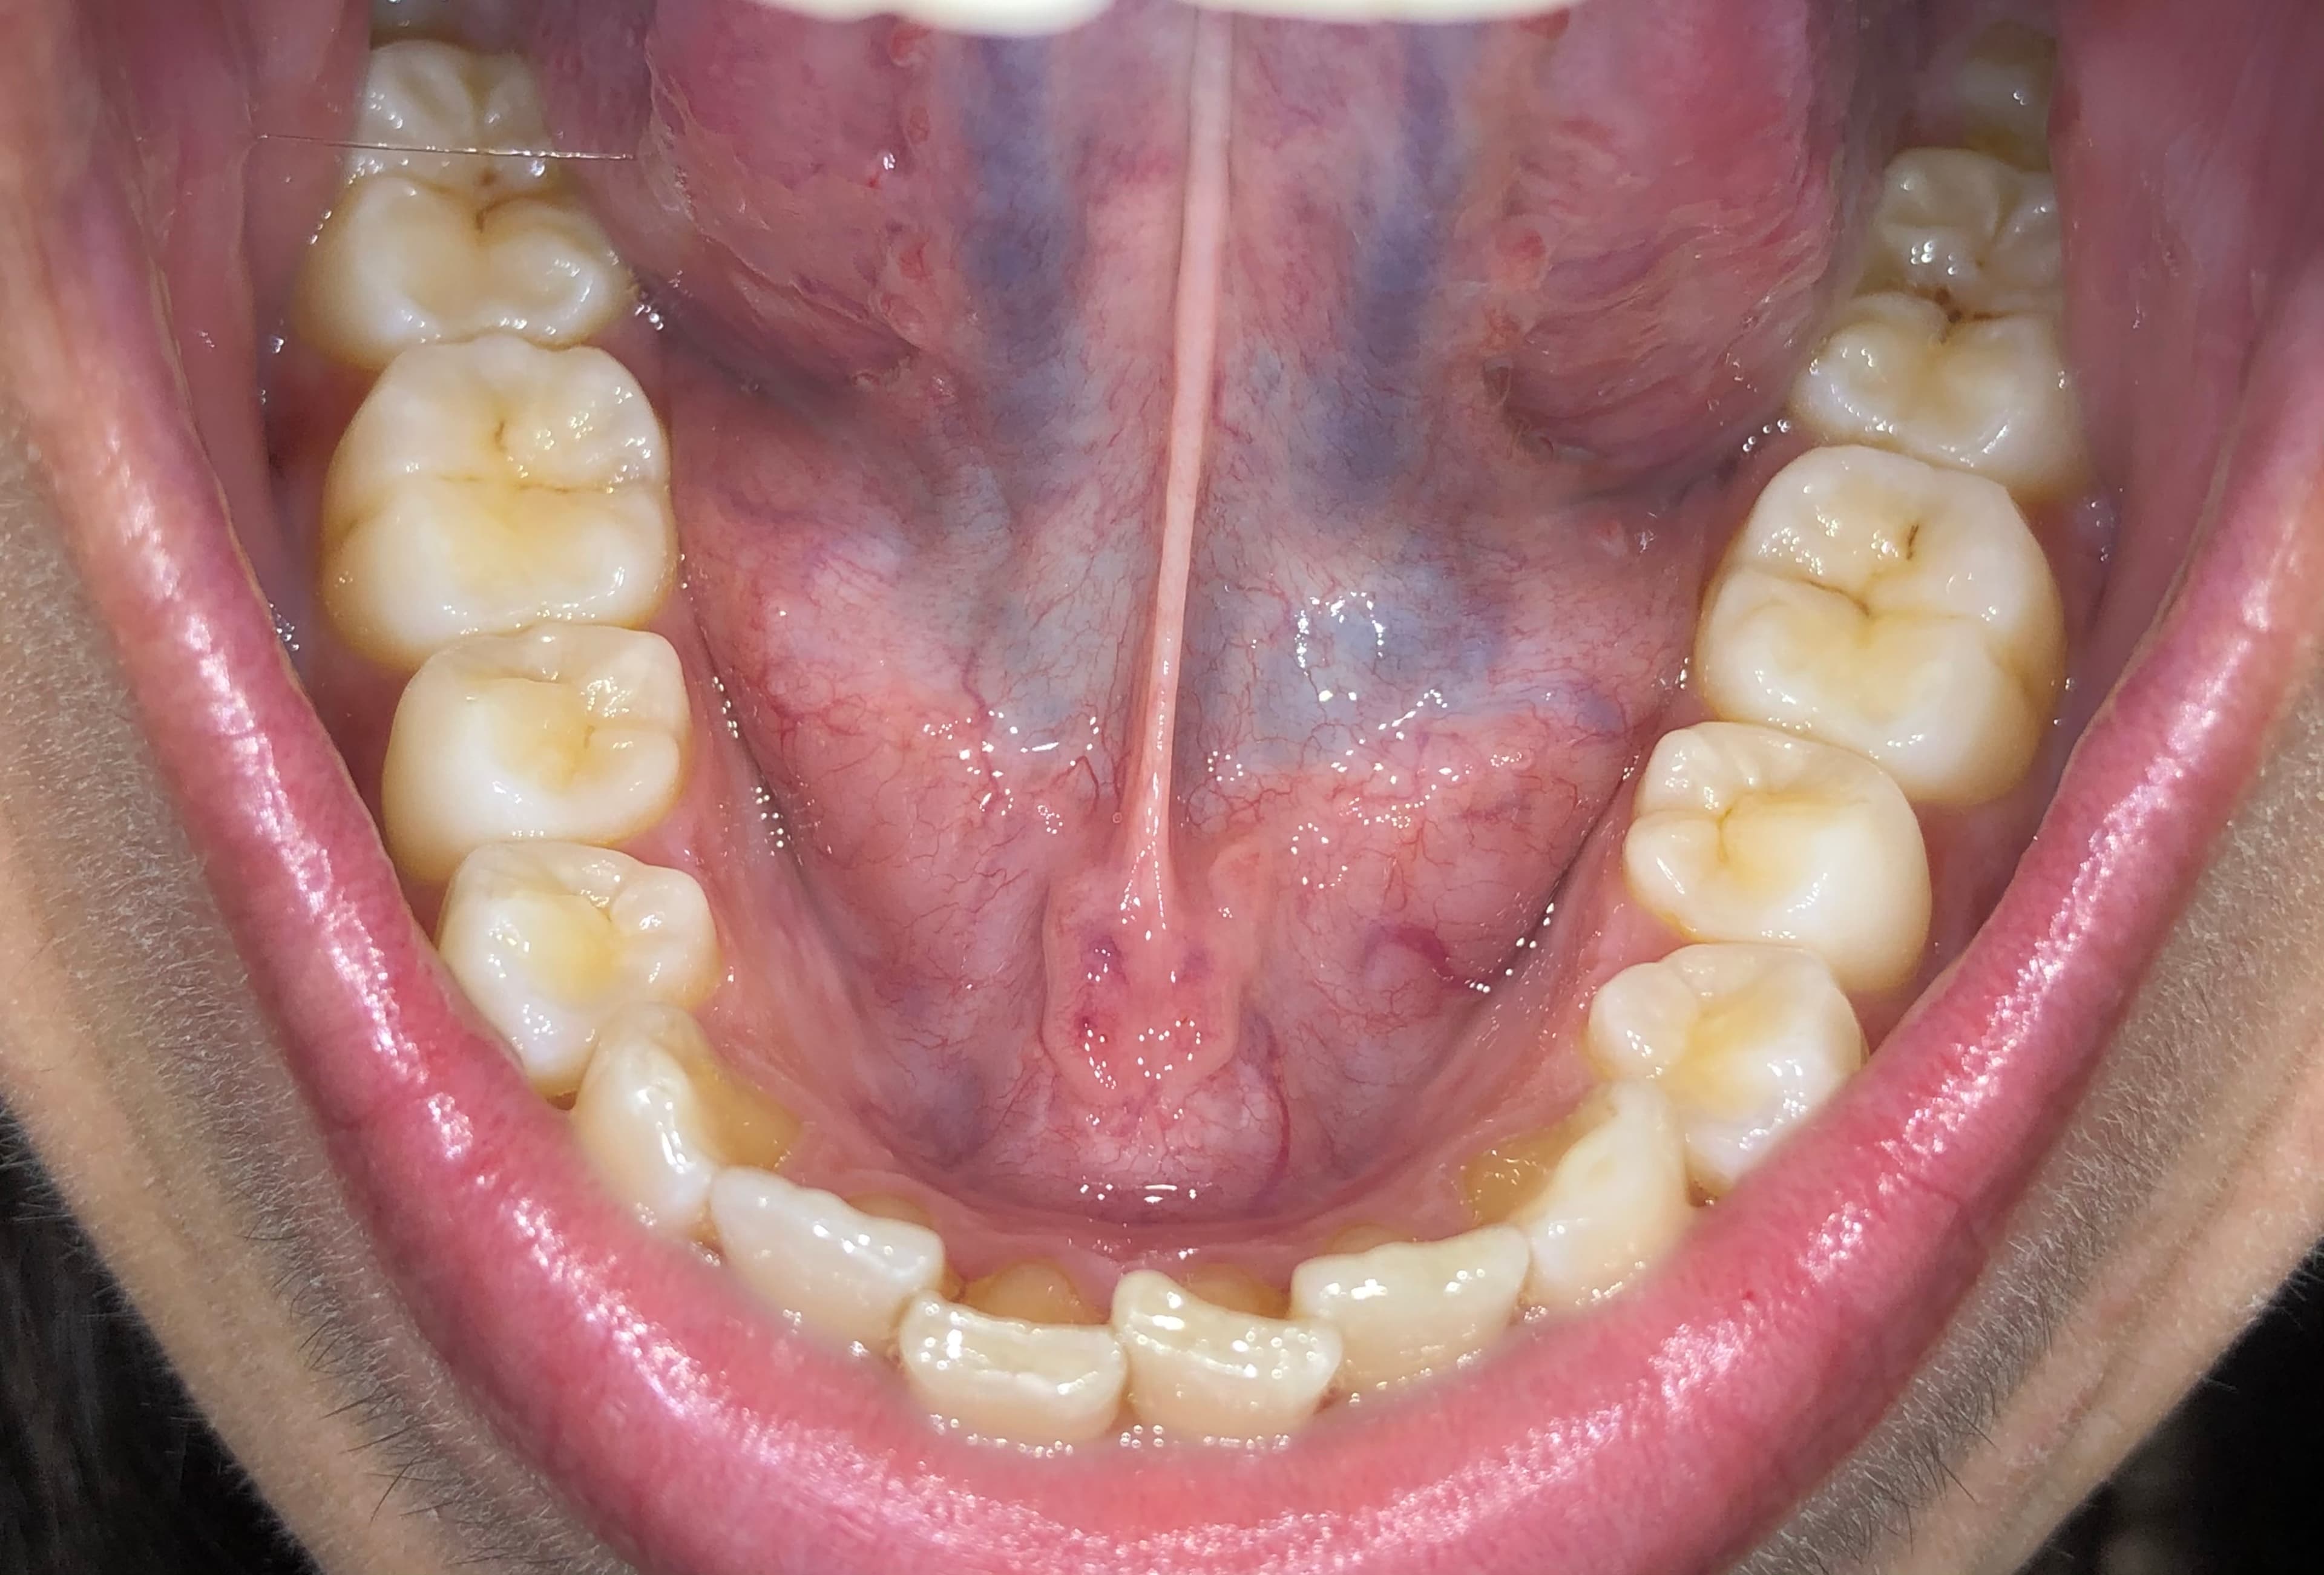

Beginning of treatment

Moderate crowding appears in the lower teeth. The first aligners apply steady pressure, guiding teeth into early movement and preparing the arch for correction.

Middle of treatment

Crowding reduces as aligners create space between teeth through controlled movement. The arch expands, and tooth rotations become more visible.